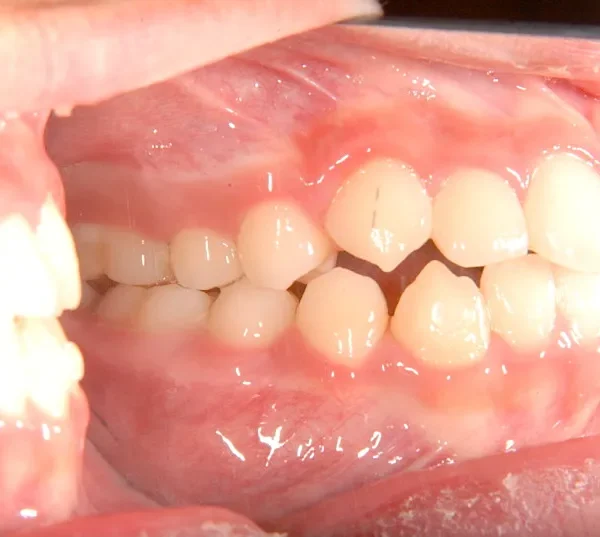

初診時年齢 小学校2年生 (男性) 主訴 癒合歯・永久歯が生えるスペースがない

診断名 叢生 装置名

上下の歯並びが狭く、永久歯の生える隙間がありません。

右下に癒合歯があり 上下の歯並びのアーチが悪くなっています。

状態 永久歯が生える隙間がない(叢生)

ガタガタ・でこぼこに生えている(叢生)